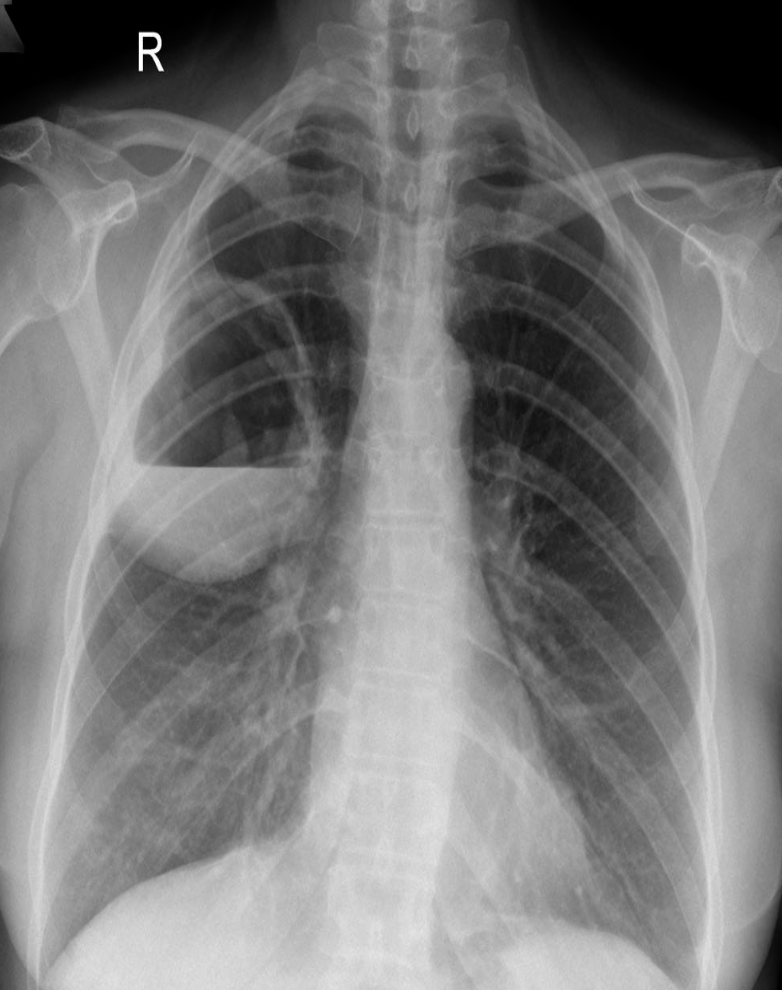

Patient with recurrent attacks of dyspnea and chest tightness after exercise. Clinical diagnosis bronchial asthma. Chest X ray is as follows:

Q1: in this chest x-ray normal or abnormal? Normal.

Q2: on chest auscultation, what added sounds can be heard in asthma? Wheeze.

Q3: Name any drug which can precipitate asthma? NSAIDS, Beta blockers.

Q4: You ordered spirometry for this pt. what will be the expected finding? FEV1 is reduced.

Q5: Name 2 clinical features of severe asthma? Z Can Not complete a sentence in one breath, Tachypnea, cyanosis

Q6: What ttt will you give in moderate to severe asthma? Name any 2. Bronchodilators, corticosteroids.